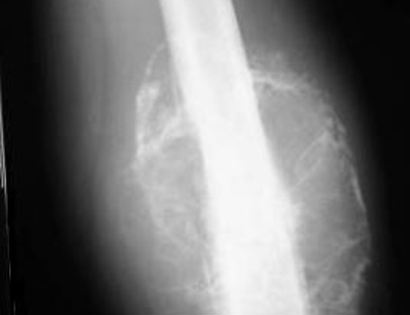

X-ray Photo

Distal Femur MRI of Tumor

Distal Femur X-ray of Tumor

You will be monitored periodically with X-Ray and MRI imaging over the course of 5 years to ensure there are no signs of recurrence. You will have follow up appointments every 4 months for the first 2 years, then every 6 months for the next 2 years, and then once a year. Since the integrity of the limb has been restored to full or almost full, recovery is anticipated provided the patient adheres to strict physical therapy.